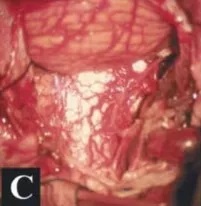

▼术中及肿瘤切除后的硬膜内部位

术后CT和MR,显示肿瘤及其被肿瘤侵犯的骨质都切除,肿瘤全切,Simpson一级切除。